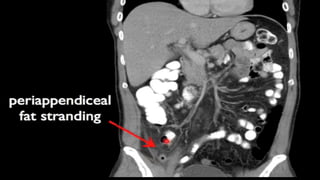

This document discusses the evaluation of right lower abdominal pain and lists appendicitis as a key cause. It notes that other potential causes include hemorrhagic cysts, heterotrophic pregnancy, salpingitis with pyosalpinx, funiculitis, and torsion of an undescended testis. The document was presented by Dr. A.S.M. Sufian of Cumilla Medical College Hospital and thanks the audience for their patience and listening.